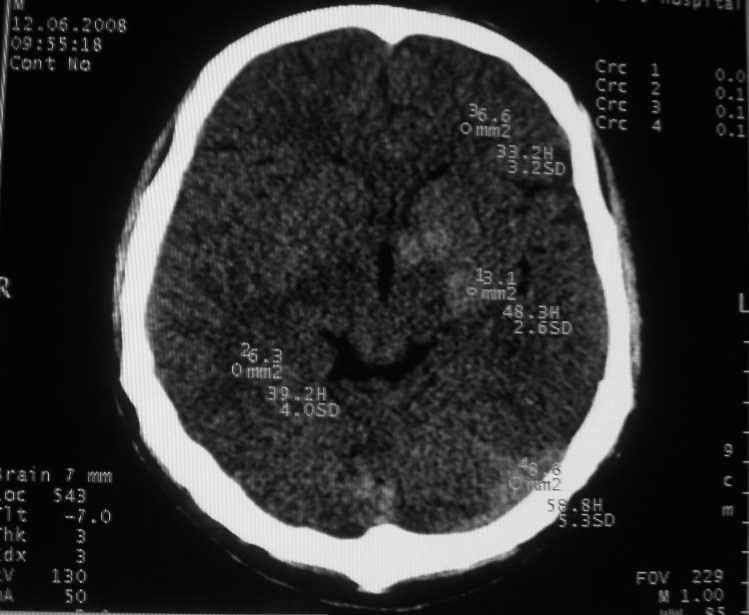

以下是引用守望可可西里在2008-6-13 1:25:00的发言:[br][br] 1.双侧大脑中动脉高密度踌型样接近于全程显示,部分大脑前动脉、基底动脉也呈高密度改变。[br] 2.右侧基底节多发类圆形ct值接近于出血的高密度,边缘模糊。双侧小脑幕及直窦、上矢状窦增宽、模糊。左侧横窦和乙状窦区密度增高、呈云雾状,内缘模糊。[br] 如果这样的表现发生在一个老年人脑部,我们首先会想到是高血压、动脉粥样硬化,就可以很容易得出结论。但这发生在一个20岁年青人的身上,且病程长达半年、临床症状不怎么重,这就比较蹊跷且应该引起高度重视了。[br] 我认为此病人应该是一个血液病患者--双侧大脑中动脉、部分大脑前动脉及基底动脉的高密度改变,只是一个假象:即相对于ct值偏低,只有35的脑灰质而言的相对高密度。而那么多出血改变,则是真正的病变表现。[br] 建议临床进一步进行其他相关的血液、骨髓检查,肝、脾也应该好好检查,应有明显的肿大。